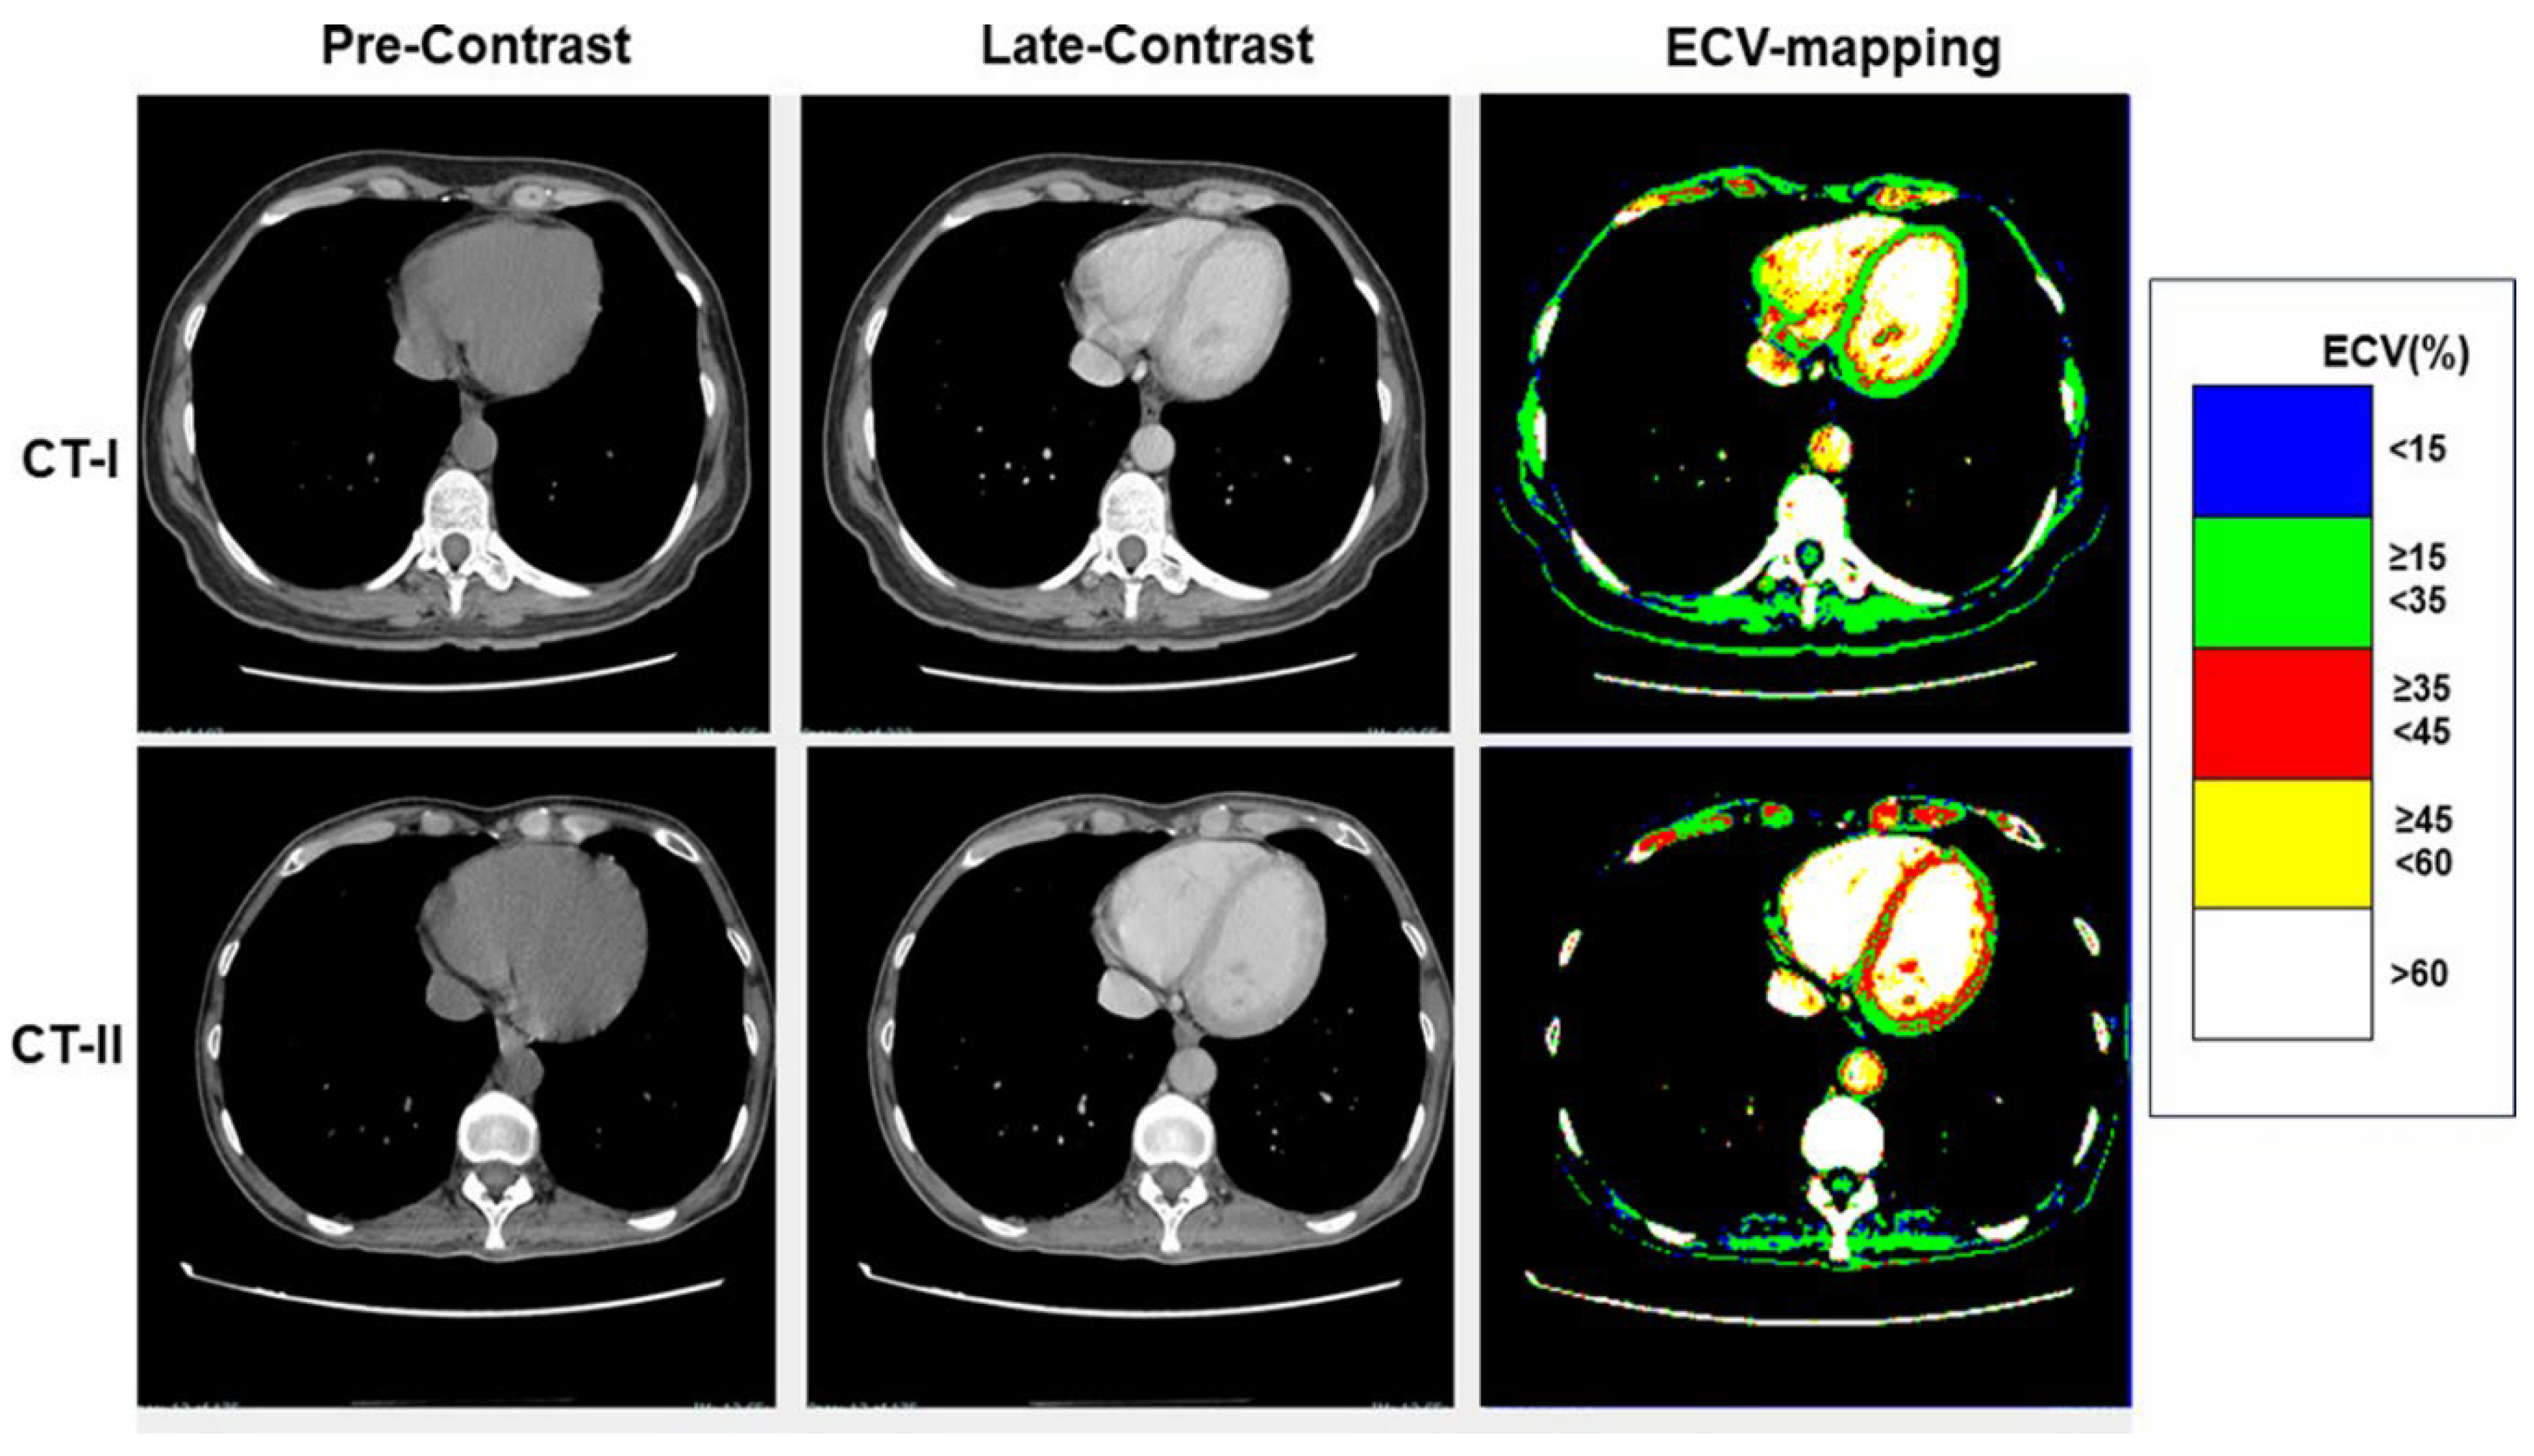

As shown in Table 3, at CT-I myocardial ECV measured in the interventricular septum and in the LV lateral wall was not significantly between High-risk and Low-risk groups, despite age and gender differences between them. Similarly, ECV of both the septum and LV lateral wall was not significantly different between the groups at CT-II. Examples of ECV maps are shown in Figure 1, Figure 2 and Figure 3.

High-risk patients showed a significant increase of both septal ECV [going from 32% (31-35%) at CT-I to 37% (35-39%) at CT-II (p = 0.0002)] and of lateral wall ECV [from 30% (27-31) to 32% (29-34) (p = 0.028)]. In contrast, the ECV change was not significant in the Low-risk group [septal ECV: from 35% (32-38) to 35% (32-39) (p = 0.16); lateral wall ECV: from 32% (29-35) to 32% (30-34) (p = 0.93)] (Figure 4). Overall, ECV increased by at least 1 percentile in 35 out of 51 (69%) High-risk patients. Among them, 15 (43%) had a diffuse myocardial increase of ECV and 20 (67%) a focal increase of ECV within the interventricular septum and/or the lateral wall.

Figure 3. ECV mapping in a patient undergoing a High-risk chemotherapy protocol. A diffuse increase of ECV can be seen at CT-II (right upper panel) compared to CT-I (right lower panel).